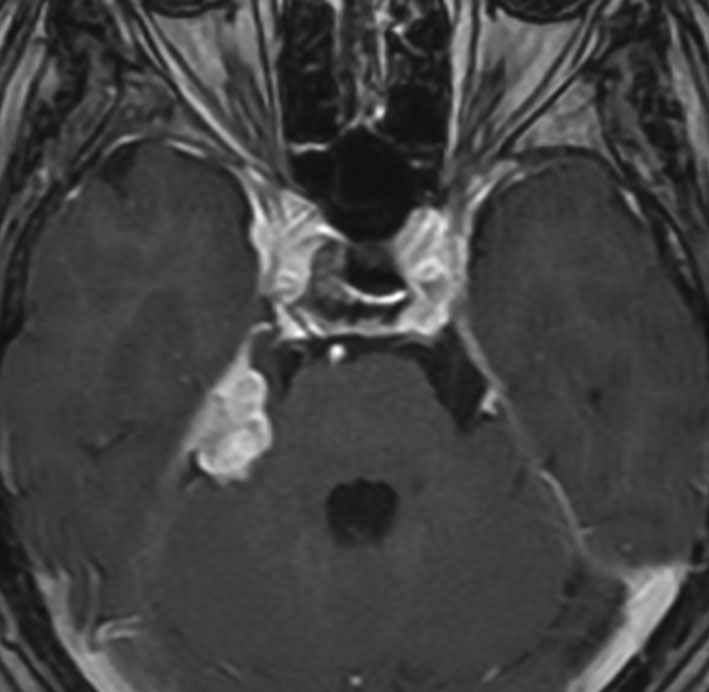

放射線誘発髄膜腫

ジャーミノーマへ44グレイの全脳照射をしてジャーミノーマは治りました。でも,15年後に髄膜腫が発生しました。典型的な放射線誘発腫瘍です。これは取れるので大丈夫!